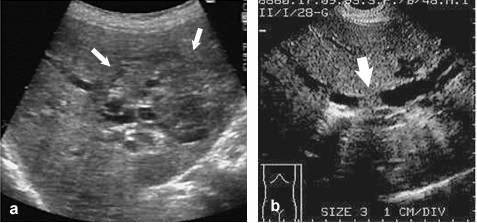

Colangiocarcinomul (CCC) este o tumora cu punct de plecare la nivelul cailor biliare sau cu etiologie mixta hepato-colangio-celulara. Se dezvolta pe ficat necirotic si nu secreta alfa-1-fetoproteina. Aspectul clinic este dominat de sindromul icteric (coloratia galbena a tegumentelor si mucoaselor, urini hipercrome, scaune decolorate, prurit tegumentar), precum si de catre sindromul de impregnare maligna. Ecografic, formatiunea tumorala poate sa fie unica sau multipla, multicentrica, cu localizare in acelasi lob sau in ambii lobi ai ficatului. Poate avea o dispozitie periferica, mai frecvent subcapsulara (cu precadere la nivelul lobului drept hepatic) (a) sau centrala, cand invadeaza hilul hepatic (tumora Klatskin) (b). Dimensiunile tumorii sunt foarte variabile, iar delimitarea este relativ neta. Haloul peritumoral este intalnit la mai putin de 1/3 din cazuri. Atunci cand are dimensiuni mici, CCC este hipoecogen, ceea il face dificil de diferentiat de chisturile hepatice, in timp ce in caz de volum mare, ecogenitatea tumorii este crescuta.Colangiocarcinomul cu diferentiere celulara inalta poate 'sparge' peretii cailor biliare si poate realiza o invazie a acestora, similara hepatocarcinomului fata de sistemul venos port. Dilatarile de cai biliare intrahepatice apar in cazul tumorilor centrale, indeosebi a tumorii Klatskin. Aceasta se insoteste de colabarea colecistului (care poate sa fie inaparent ecografic) si de prezenta de structuri limfoganglionare la nivelul hilului hepatic.

Colangiocarcinom: a. localizare periferica (sageti); b. localizare la nivelul hilului hepatic (tumora Klatskin) (sageata)